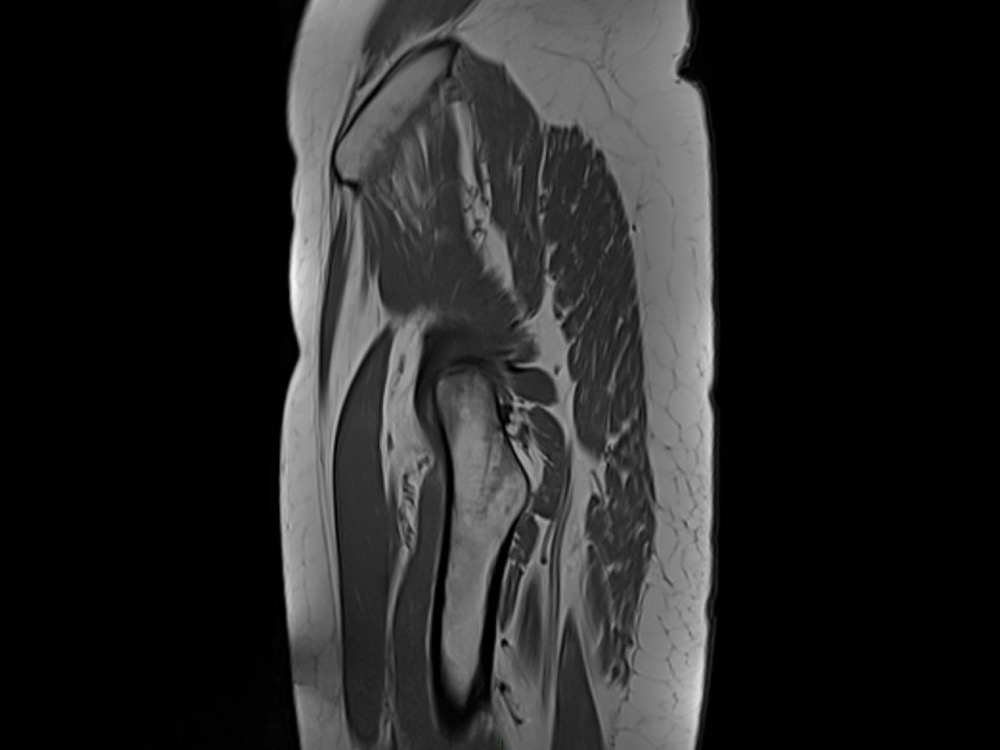

Aboudaram / Burns 11/01/2023